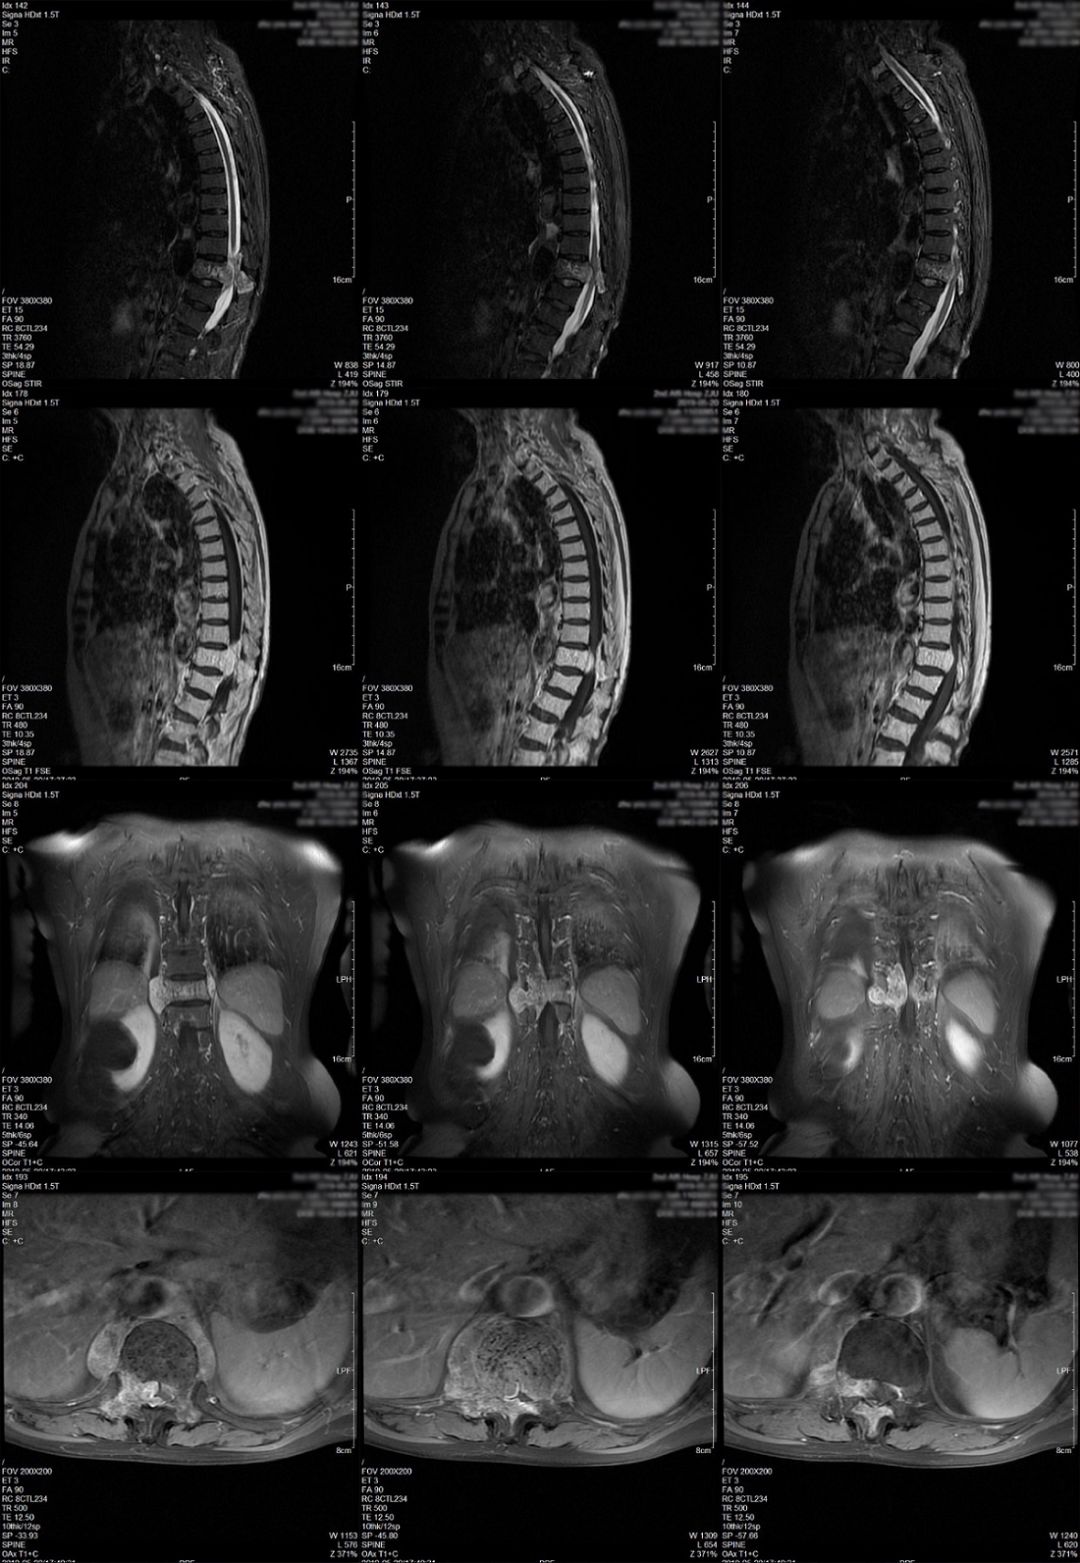

术后患者下肢无力症状较术前部分缓解,查体双下肢肌力III级(术前右下肢肌力II级),复查MRI(图3)及CT(图4)见胸10-11椎板及棘突切除后改变,胸11椎管内病变大部切除,硬膜囊及脊髓受压明显缓解。术后第6天转康复科进一步治疗,建议根据康复情况择期行放射治疗。

图4.术后第4天复查胸椎CT平扫示胸10-11椎板及棘突切除,术区无明显出血。